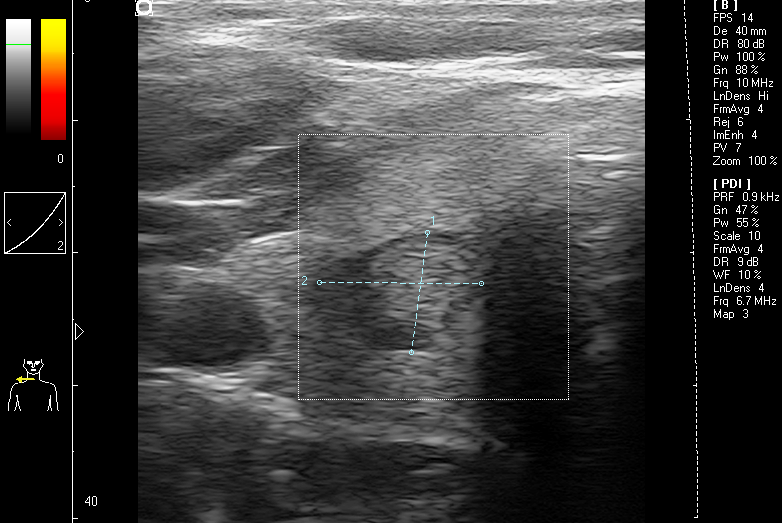

Ultraschall – Halsschlagader längs m. Karotis-Intima-Messung